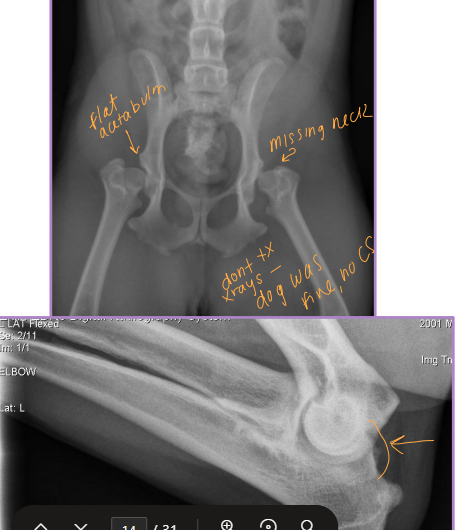

Diagnostic Imaging for Hip Dysplasia

VD most useful

Want >50% acetabular coverage!

Rads: Bone shape, remodeling, osteophytosis(neck), enthesiophytosis (Morgan’s line), laxity

Do not treat the radiograph!

CT + MRI: not useful and expensive